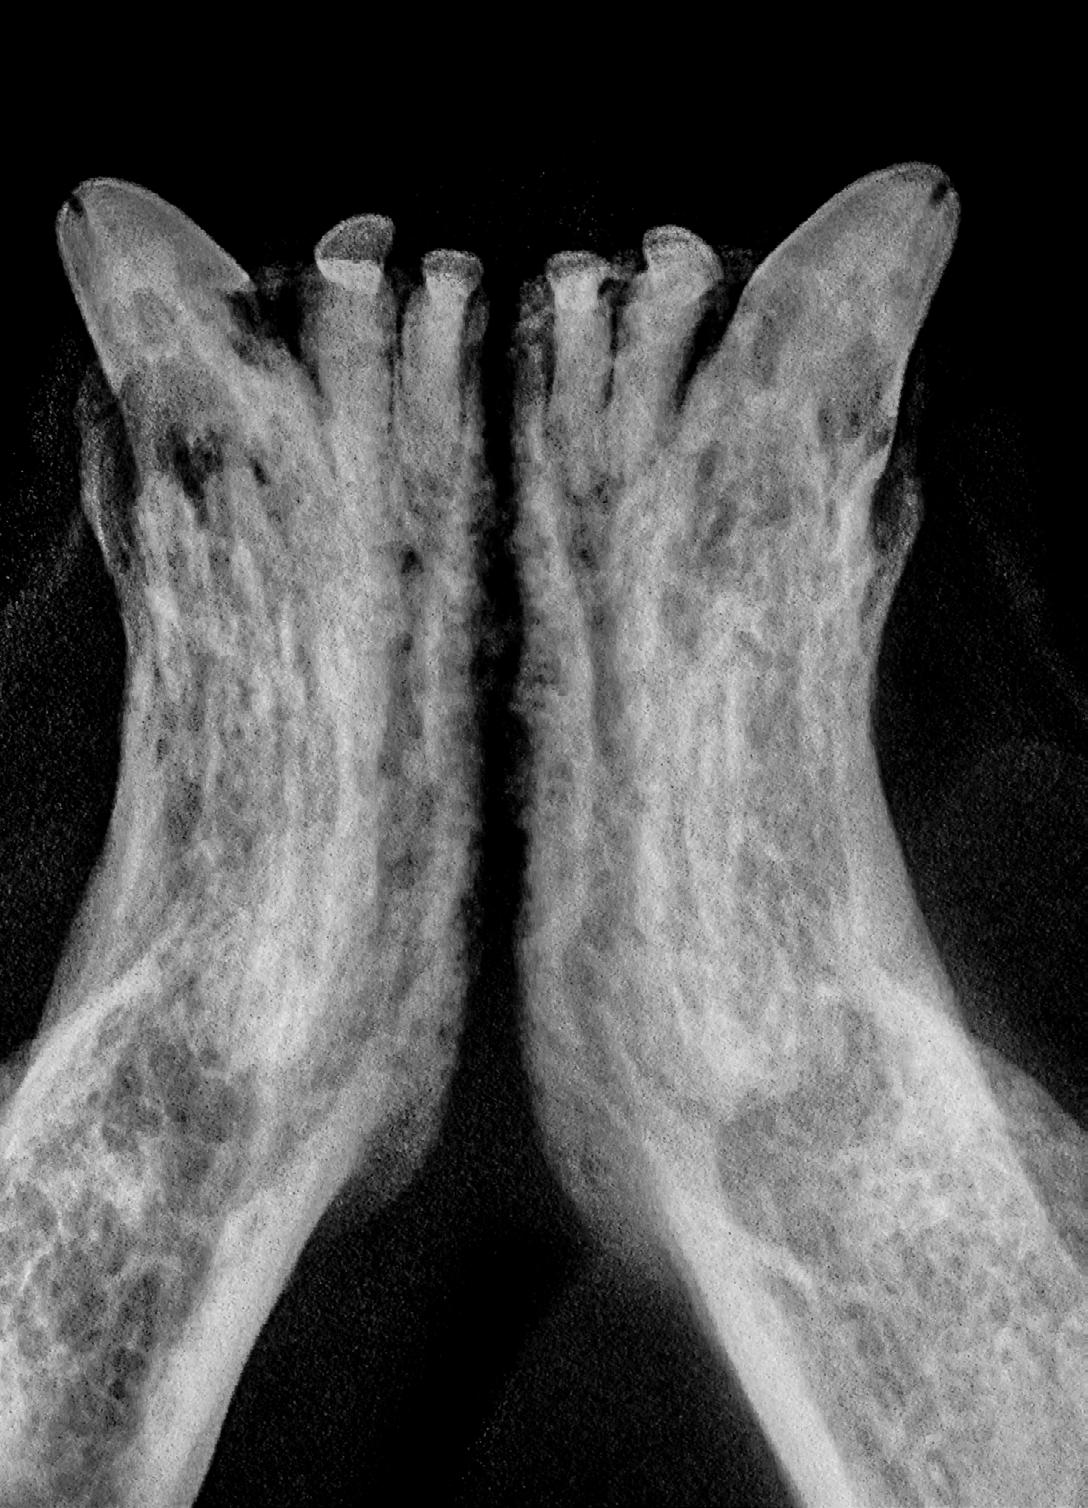

Alveolar bone expansion clinically appears as bulging alveoli around one or both maxillary and/or mandibular canines. Radiographically, this lesion appears as bone loss around the root and expansile alveolar bone growth.

Figure 5A: Bilateral canine alveolar bone expansion. Figure 5B: Intraoral radiograph consistent with bone expansion. Image courtesy of Dr. Jan Bellows.